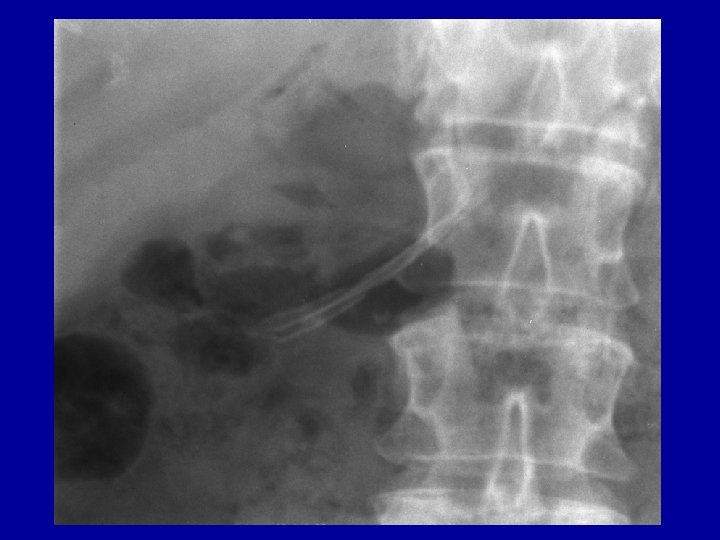

Case report VII. • 2010 Jan. Moderate pain, chronic cholangitis • ALP: 542 U/l, GGT: 205 U/l, glucose: 9, 3 mmol/l, CRP: 66 mg/l • US: Progressive parapapillary calcification, dorsal pancreatic duct 14 -18 mm with some parenchymal inflammation in the head of pancreas • Fatty liver with portal inflammation

Case report VIII. • 2010 Febr. ERCP: Pancreas divisum with unequivocal changes in the ventral ducts. • Patulous secondary papilla with suprapapillary restenosis and distal dilatation of dorsal duct, • Dilation, 10 F pancreatic stent + 5 F nasopancreatic catheter with citrate lavage for 3 days followed by another 10 F stent placement into the dorsal duct

Case report IX. • 2010 Apr. another 10 F pancreatic stent to calibrate stenosis equilibrating prestenotic dilatation (10 mm=3 x 10 F), • no pain at dilation and further on. • Planned removal after 6 month